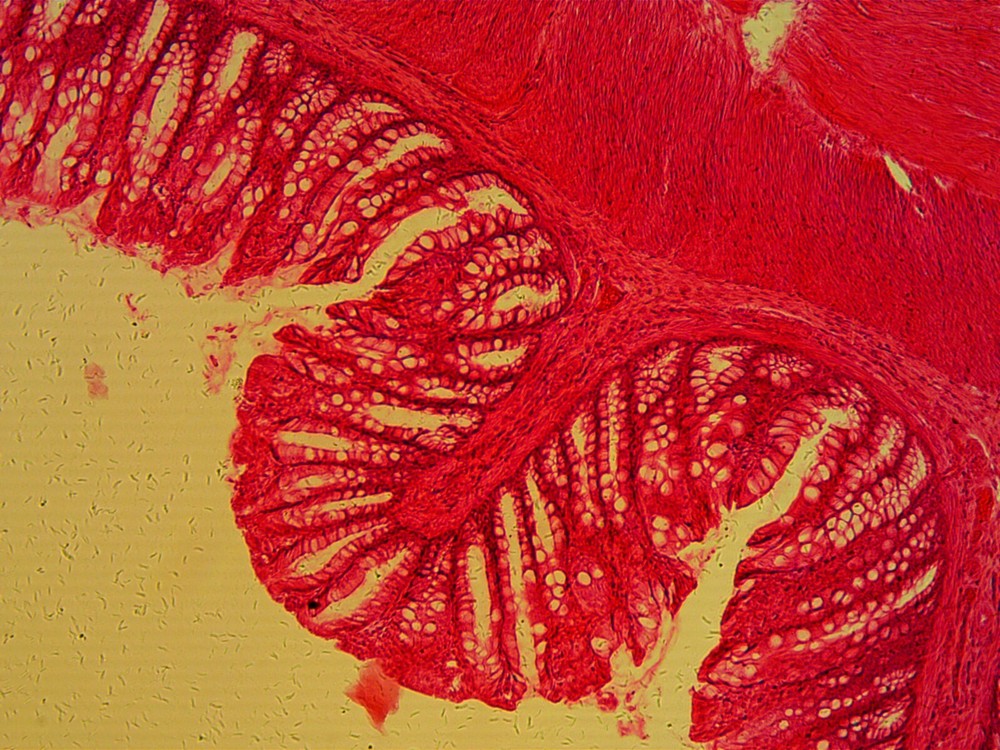

| Brand | American Optical |

|---|---|

| Microscope Structure | Upright |

| Microscope Type | Compound Microscope |

| Magnification Range | 100X & 430X |

| Model | 60 |

| Viewer | Monocular |

| Country of Origin | United States |

Check the listing for details. *Sale* Reconditioned AO Compound Microscope, 100X, 430X!. Condition: Seller refurbished, Made in United States. Listed at 89.95 USD. Options included are2 Objective turret, and light, and coarse and fine focus. Two AO Objectives, 10X and 43X, yieldingmagnifications of 100x and 430X Optics Clear and sharp. Made in USA.